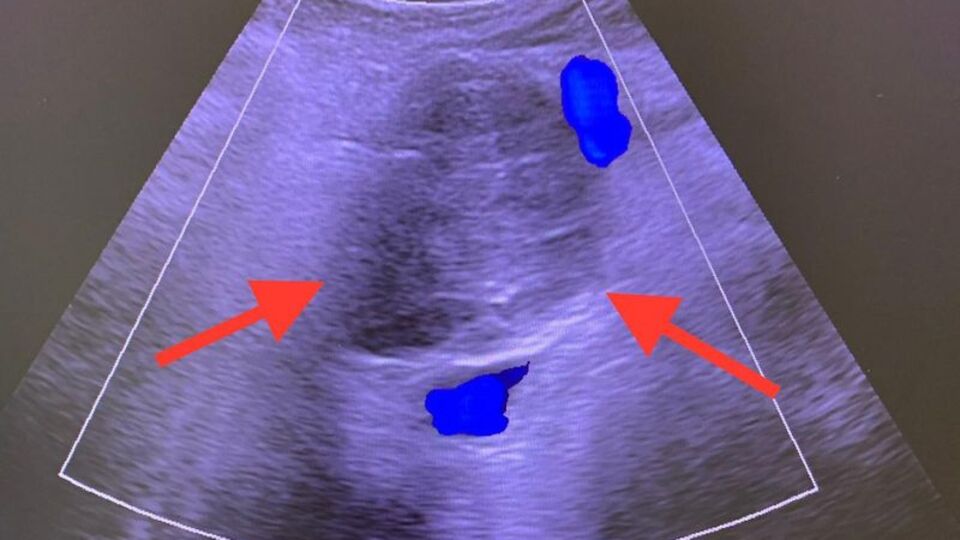

Hastanın 2010 yılında kendisine başvurduğunu belirten Radyoloji Uzmanı Doç. Dr. Mir Ali Purbager, "Renkli ultrason eşliğinde damarlar korunarak kitleye kapalı olarak ablasyon tedavisi uygulandı. Pankreas kanserinin sebebi kesin olarak bilinmemekle birlikte obezite, sigara ve alkol kullanımı, yağlı yemekler, az sebze ve meyve tüketimi, diyabet, kronik pankreatit, mide ameliyatı ve aile öyküsü gibi faktörlerin rolünün olduğu düşünülmektedir. Pankreas kanseri sinsi bir hastalık olup tanı anında hastaların yüzde 52’sinde yaygın hastalık, yüzde 26’sında bölgesel yayılım mevcut olup hastaların ancak yüzde 15-20’sinde kitle cerrahi olarak çıkarılabilir aşamadadır. Pankreas kanserinin bir yıllık genel sağ kalım oranı yüzde 26, beş yıllık ise yüzde 6’dır. Pankreas kanserinde kitle damarları sarmadıysa ve metastaz yoksa ilk tedavi seçeneği Whipple (pankreas başı, bu bölgeye yakın safra yolları ve 12 parmak bağırsağı tümörlerinde uygulanan) ameliyatıdır. Ancak hastalık sinsi ilerlediğinden genellikle tanı aşamasında ameliyat şansını yitirmektedir” ifadelerini kullandı.

Ameliyat şansını yitiren hastalarda girişimsel işlemler, kemoterapi ve radyoterapiyle yaşam süresini uzatmanın söz konusu olabildiğini kaydeden Doç. Dr. Purbager, “Pankreasın anatomik konumu nedeniyle ana damarlarla çok yakın ilişkisi mevcuttur. Ayrıca karın boşluğunun arkasında yer aldığından komşuluğundaki organlardan bu organa ve tümöre ulaşmak zordur. Girişimsel işlemler büyük bir tecrübe gerektirmektedir. Hastamıza 2009 yılında pankreas kanseri tanısı koyulmuş, başka bir merkezde ameliyata alınmıştır. Ancak ameliyat esnasında kitlenin damarlara yapıştığı anlaşılarak biyopsi alındıktan sonra kitle çıkarılmadan ameliyat sonlandırılmıştır. Hastamız 2010 yılında bize başvurduğunda kitlenin 5 santimetre çapında, çevre organlara ve damarlara yapışık olduğu görüldü. Bunun üzerine açık cerrahi yapmadan kapalı olarak renkli ultrasonla damarlar korunarak kitleye mikrodalga ablasyon (yakma) tedavisi uygulandı. Komplikasyonsuz olarak tamamlanan işlemden 1 gün sonra hasta taburcu edildi. Aralıklı olarak hasta kontrolleri yapıldı. 2 yıl sonra kitlede hafif boyutsal artış izlenince tekrar kapalı yöntemle etanol ablasyon tedavisi uygulandı. 2022 yılına kadar stabil olarak seyreden kitlede 1 cm boyut artışı saptanınca 3. kez etanol ablasyon uygulandı. Bu yöntemlerde amaç tümörün büyümesinin durdurulması, engellenmesidir. Bu 12 yıl süre zarfında hasta aktif olarak yaşamını sürdürüyor, mesleği olan çiftçiliği, arıcılığı yapıyor. Burada vurgulanması gereken bir nokta pankreas kanseri tanısı alan hastalarda cerrahi şansı varsa ilk tedavi yönteminin cerrahi olduğunun bilinmesidir. Ablasyon tedavisi sadece cerrahi şansı olmayan hastalara uygulanmaktadır ki hastamız Celal Açıkgöz de böyle bir hastaydı. Radyolojik girişimsel yöntem uyguladığımız hastamız 13 yıldır pankreas kanseriyle normal hayatını yaşıyor. Şu an tümör stabil, 6 cm. takip edilecek, gerekirse tekrar ablasyon uygulanabilir” diye konuştu.